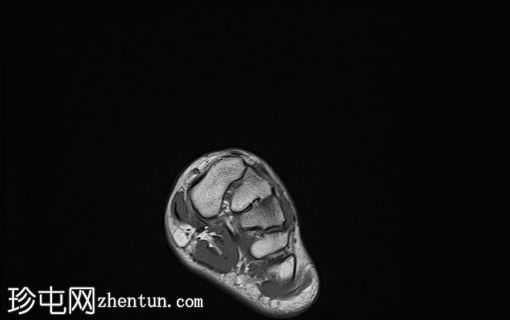

4.jpg

轴向

T1

舟骨呈二分状,分为两个骨块——较大的内侧骨块和较小的外侧骨块。

内侧骨折块外侧面呈“逗号状”,舟骨相对于距骨头轻微向内移位。

外侧骨折块及其外侧均呈斑片状T1低信号和PD FS高信号,并伴有硬化和微小囊肿,提示软骨联合/纤维界面存在慢性应激反应或退行性改变,可能伴有缺血性坏死。

双分舟骨区域外未见急性骨折线或骨髓水肿。

周围跗骨和关节未见明显异常。

未见明显软组织异常或关节积液。